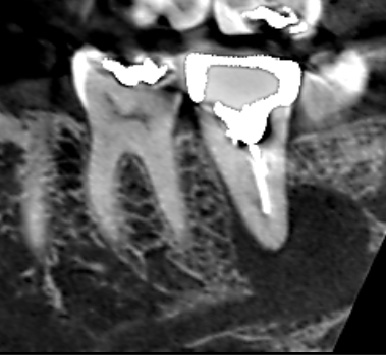

半年後、経過観察のCT画像です。大きかった膿の影が縮小し骨の再生が認められます。